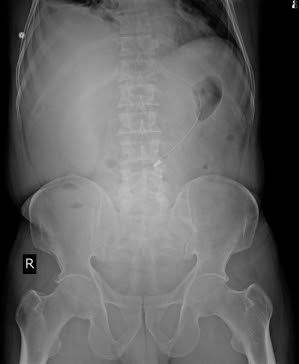

- Fever - since 2 days which was a low grade, continuous fever associated with chills and rigor. It was relieved on taking medication.

9) Abdominal X-ray: